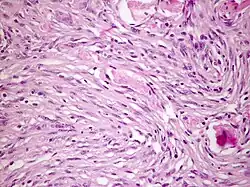

Meistens befinden sich Meningeome an der Falx cerebri, am Keilbeinflügel, an der Olfaktoriusrinne und setzen sich in der Regel gut vom angrenzenden Hirngewebe ab. Die Schnittfläche sieht grau und körnig aus. In manchen Formen ist im Mikroskop eine Zwiebelschalenformation der Tumorzellen zu beobachten. Verkalken diese, werden sie Psammomkörper genannt.

Histologie: Bestimmte morphologische Varianten werden direkt einem bestimmten WHO-Grad zugeordnet. So werden meningeotheliomatöse, fibromatöse, sekretorische, mikrozytische, transitionale, psammomatöse und angiomatöse Meningeome zu den WHO-Grad-I-Tumoren gezählt. Das chordoide und das klarzellige Meningeom entsprechen einem WHO Grad II, während papilläre und rhabdoide Meningeome zu den WHO-Grad-III-Meningeomen gerechnet werden.